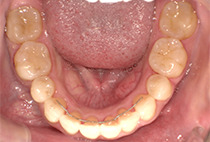

また、気になっていたオトガイ(顎先)の左右差に対して、

を行い、フェイスラインも自然に整えました。

矯正は「歯並びを治す」だけではありません。

当院では、呼吸・噛み合わせ・顔貌バランス・美容までトータルに整える顎顔面治療を行っています。